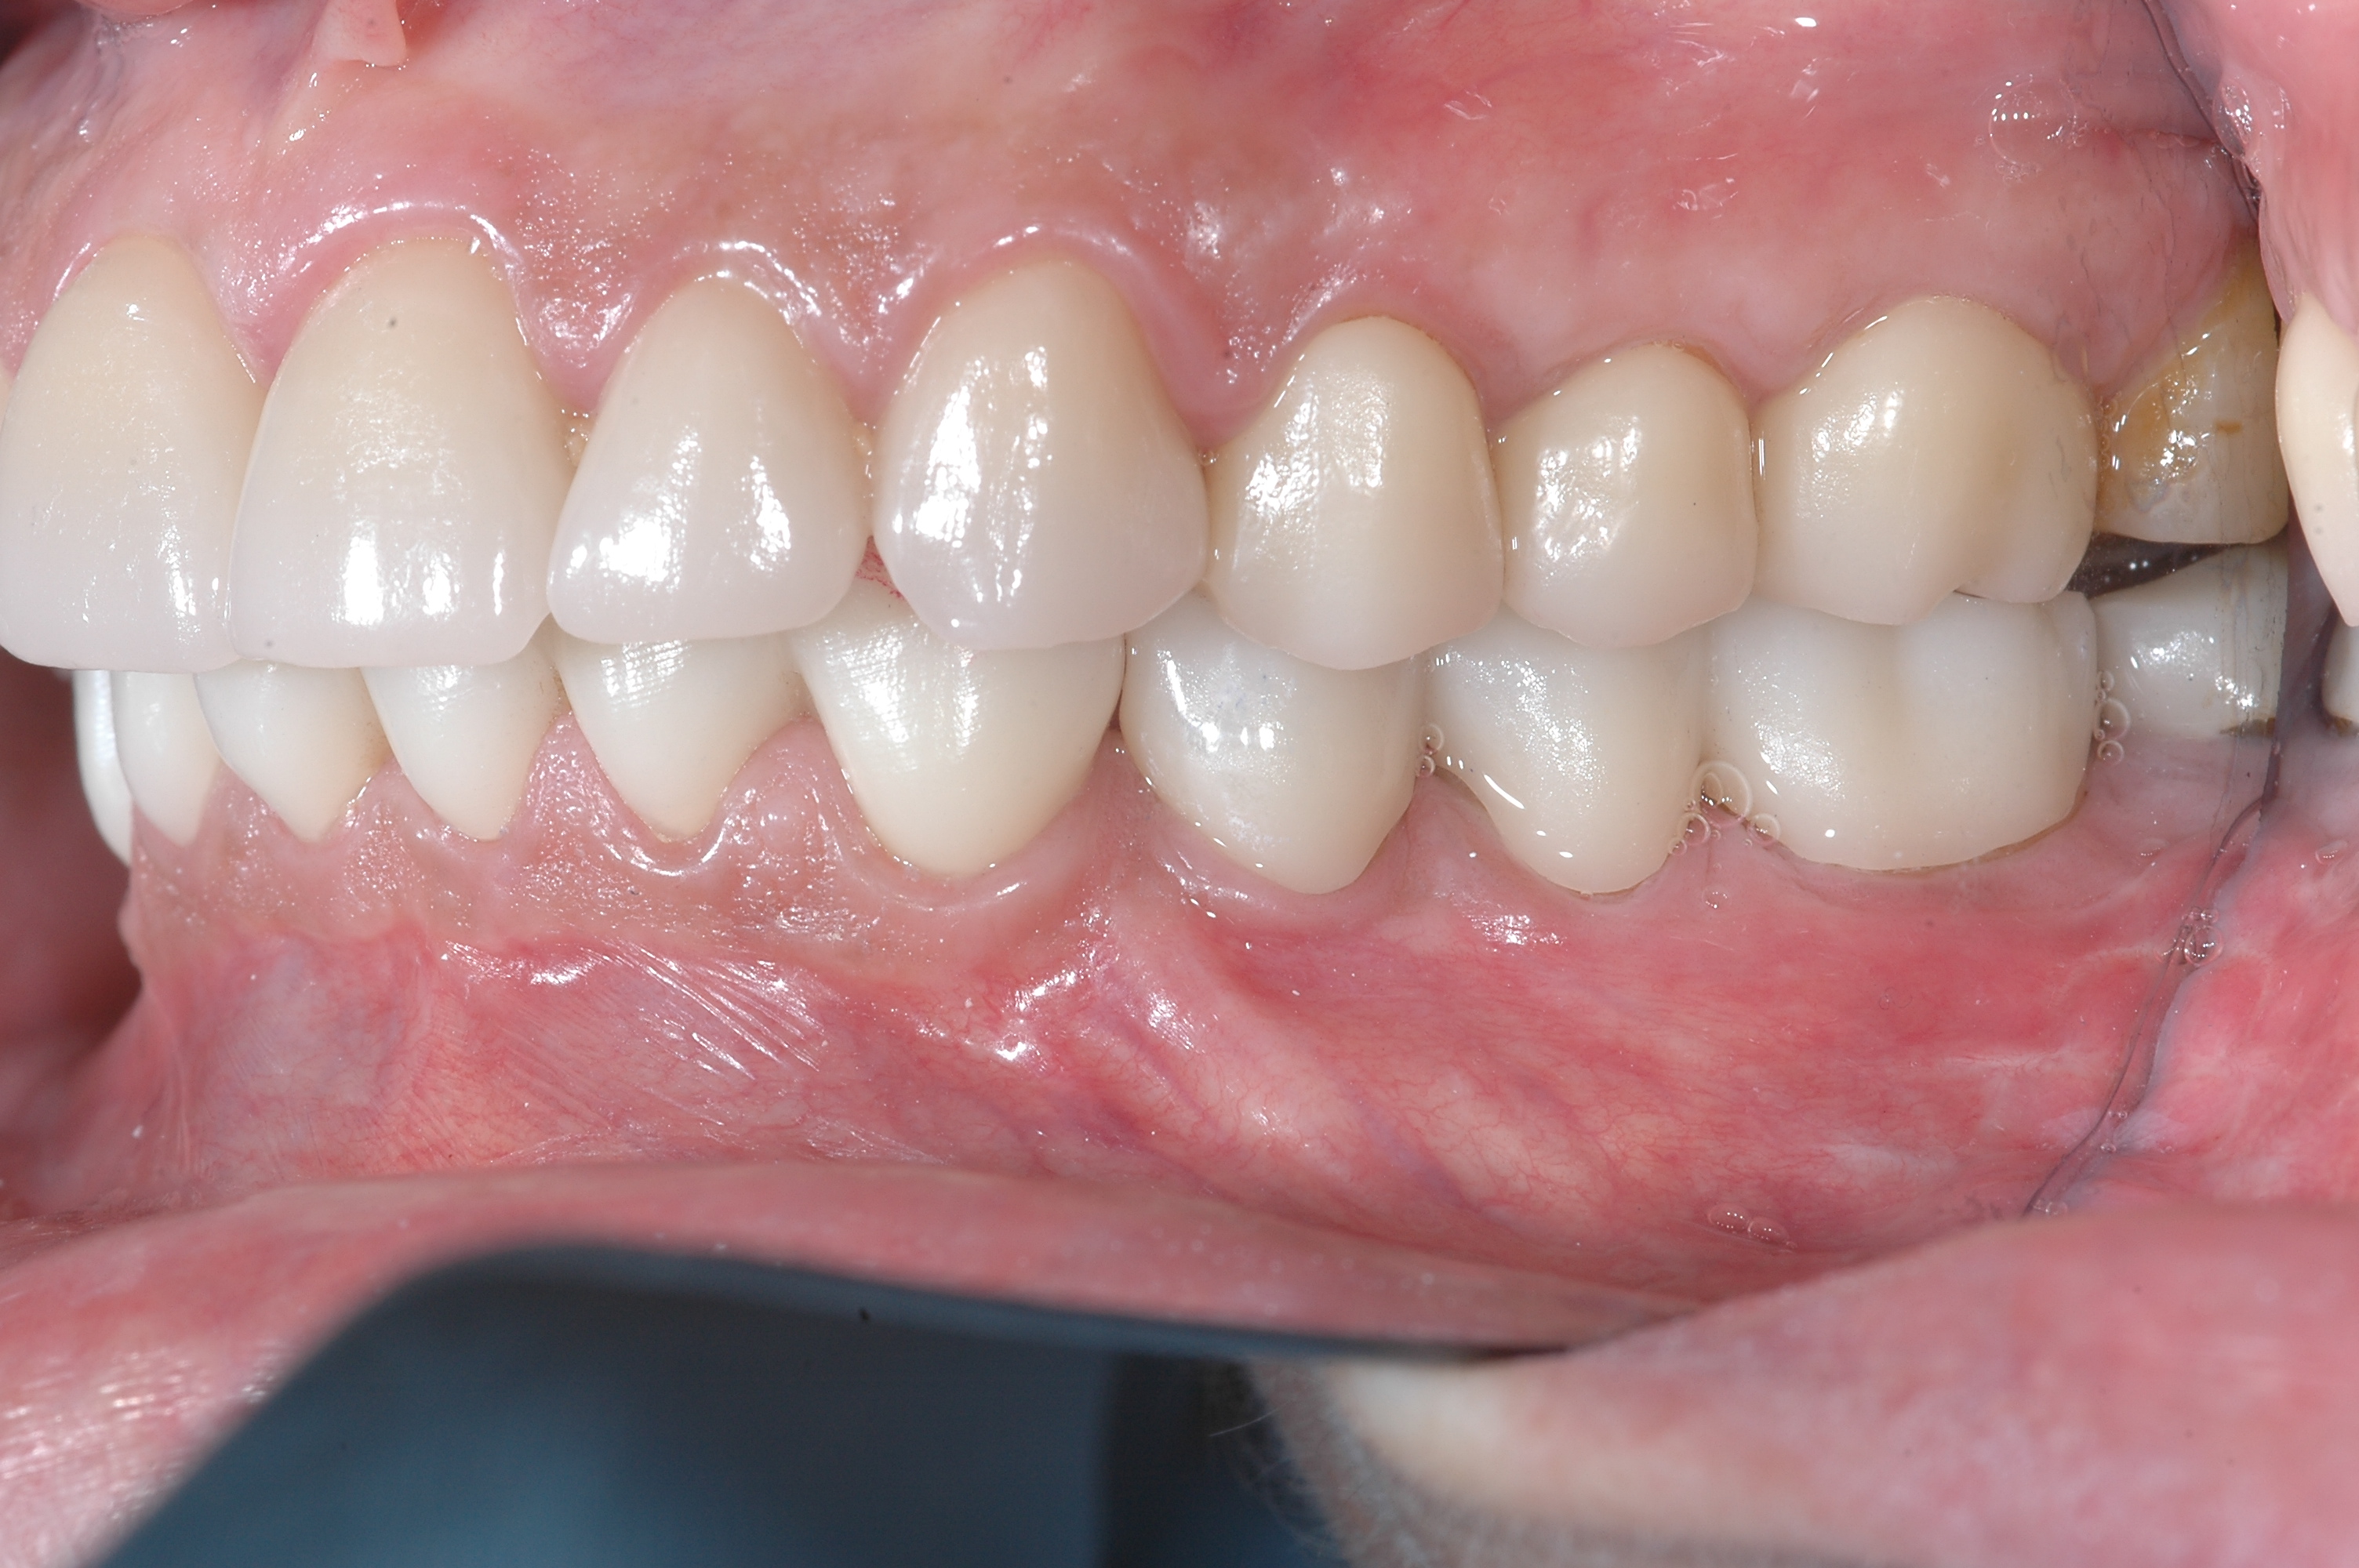

Scénarios diagnostiques récurrents observés au sein du Masticationpedia Network (et non des rapports de cas isolés). Tous les centres du Network habilités utilisent des technologies et des méthodologies neurophysiologiques permettant des diagnostics précoces et précis de pathologies imitant des symptomatologies odontologiques, telles que les Troubles Temporo-Mandibulaires et les Douleurs Orofaciales, qui peuvent parfois masquer des atteintes organiques neurologiques et systémiques. En outre, le savoir-faire acquis permet un contrôle et une finalisation des traitements orthodontiques, prothétiques et implantoprothétiques optimisés selon les réponses neurophysiologiques trigéminales, et non uniquement sur des paramètres de forme et d’esthétique.

Réhabilitations implantoprothétiques